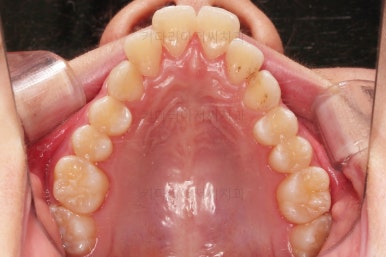

교합이 잘 맞아졌고요.

위아래 앞니도 서로 가까워졌어요.

치열도 가지런해졌고, 과개교합도 잘 개선이 되었습니다.

연산동치아교정 이제 전후 사진을 비교해 볼게요.

아래 앞니가 2개인 것이 표시가 안날 정도로 자연스럽게 교합이 맞아졌습니다.